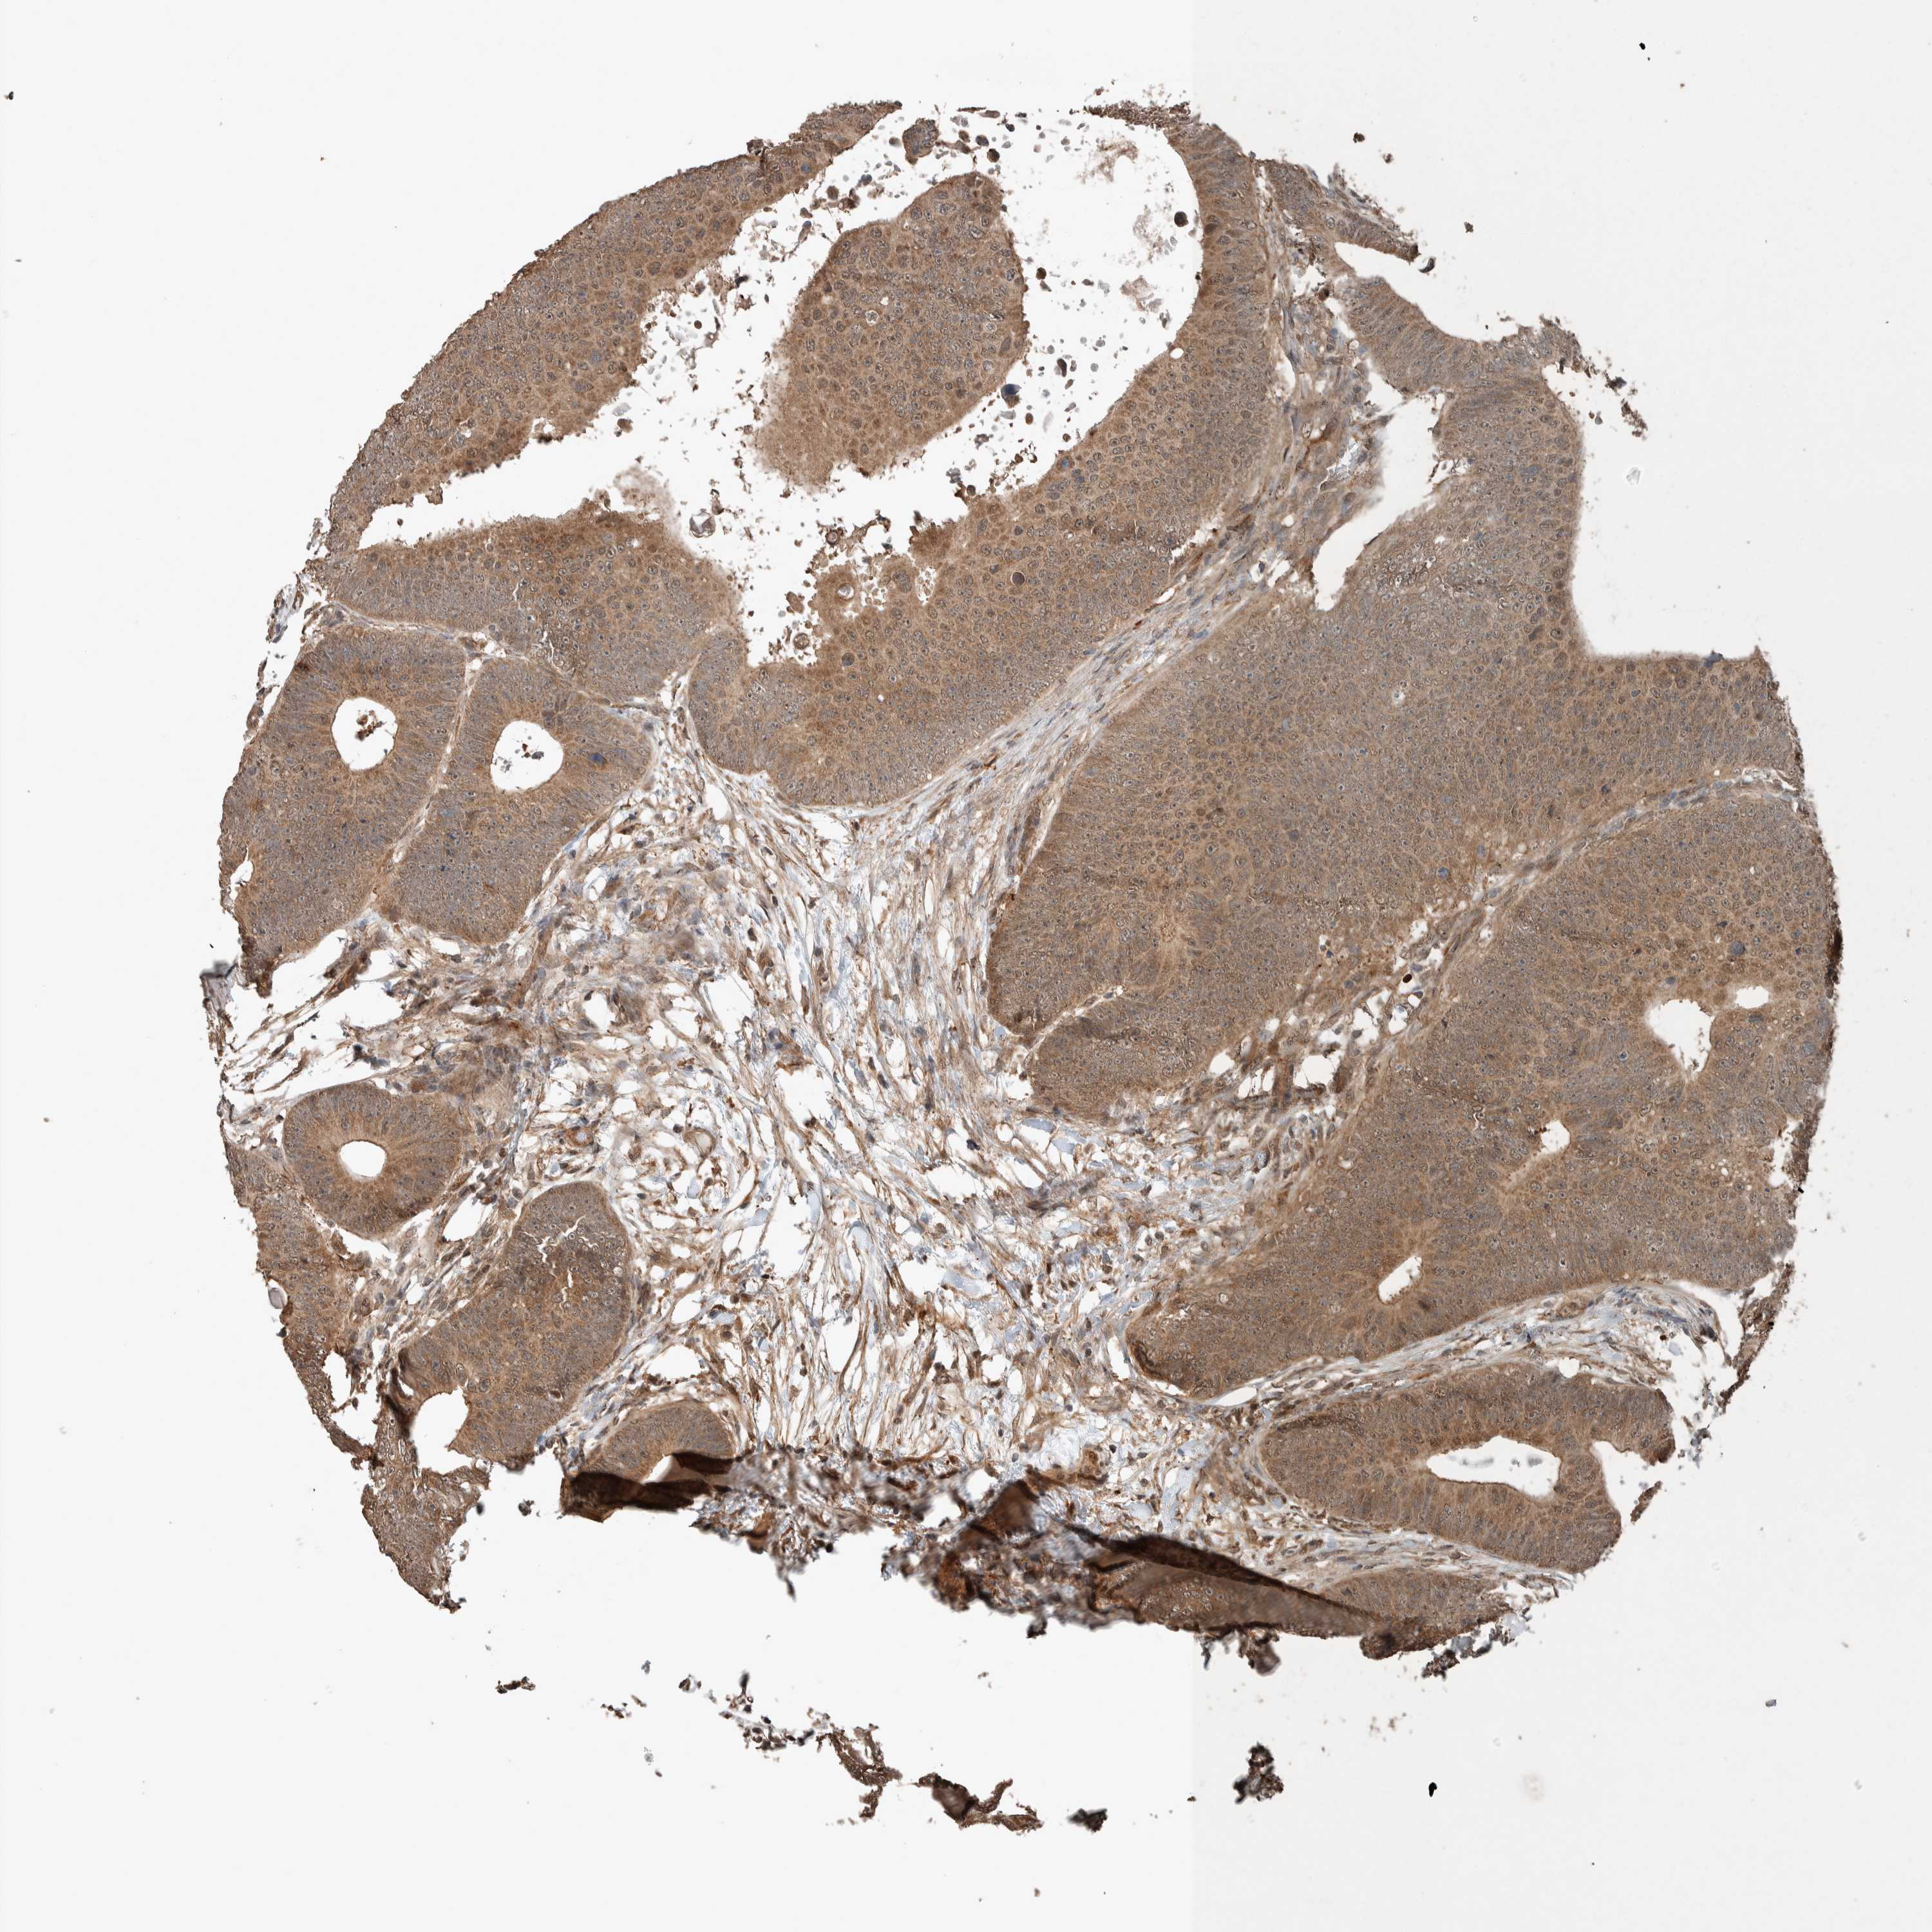

CANCER COLORECTAL CANCER Show tissue menu

Colorectal cancer

Human cancer

Colon adenocarcinoma